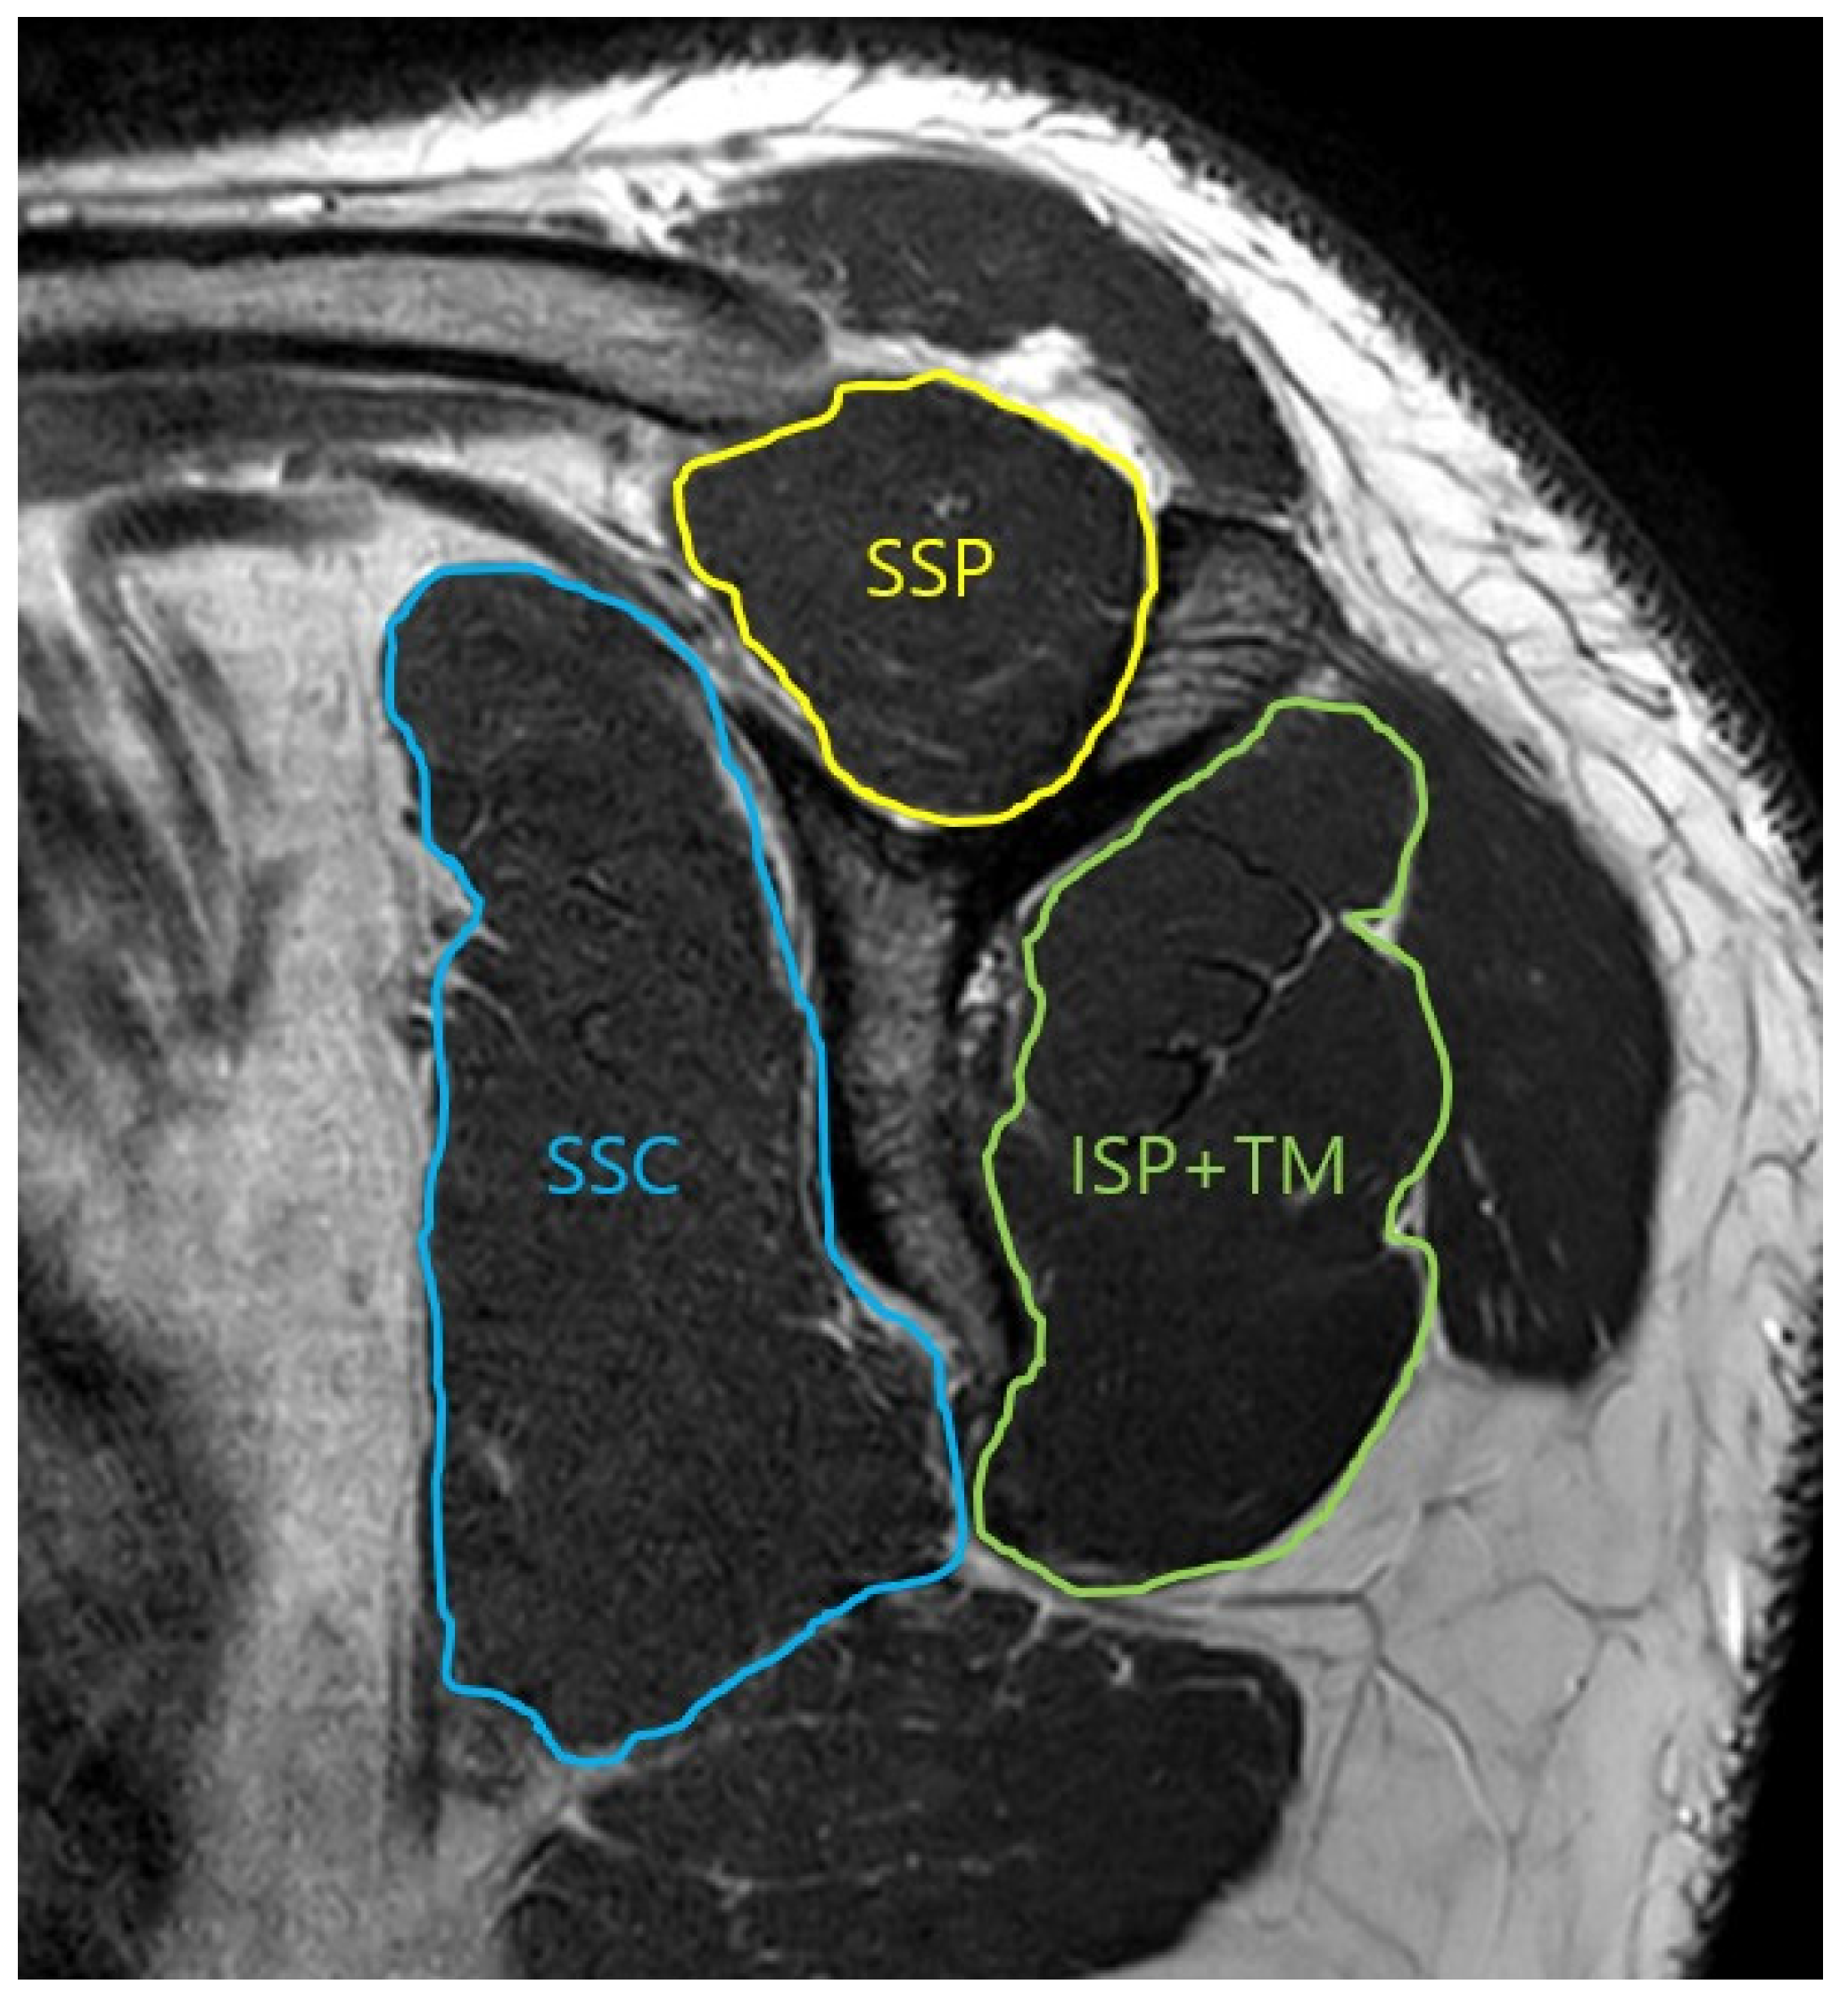

2.2. Muscle Area Measurement

| Y view SSP | 0.957 | 0.881 | 0.0001 |

| Y view SSC | 0.929 | 0.853 | 0.0001 |

| Y view ISP/TM | 0.914 | 0.869 | 0.0001 |

| Glenoid face view SSP | 0.959 | 0.911 | 0.0001 |

| Glenoid face view SSC | 0.901 | 0.899 | 0.0001 |

| Glenoid face view ISP/TM | 0.898 | 0.904 | 0.0001 |